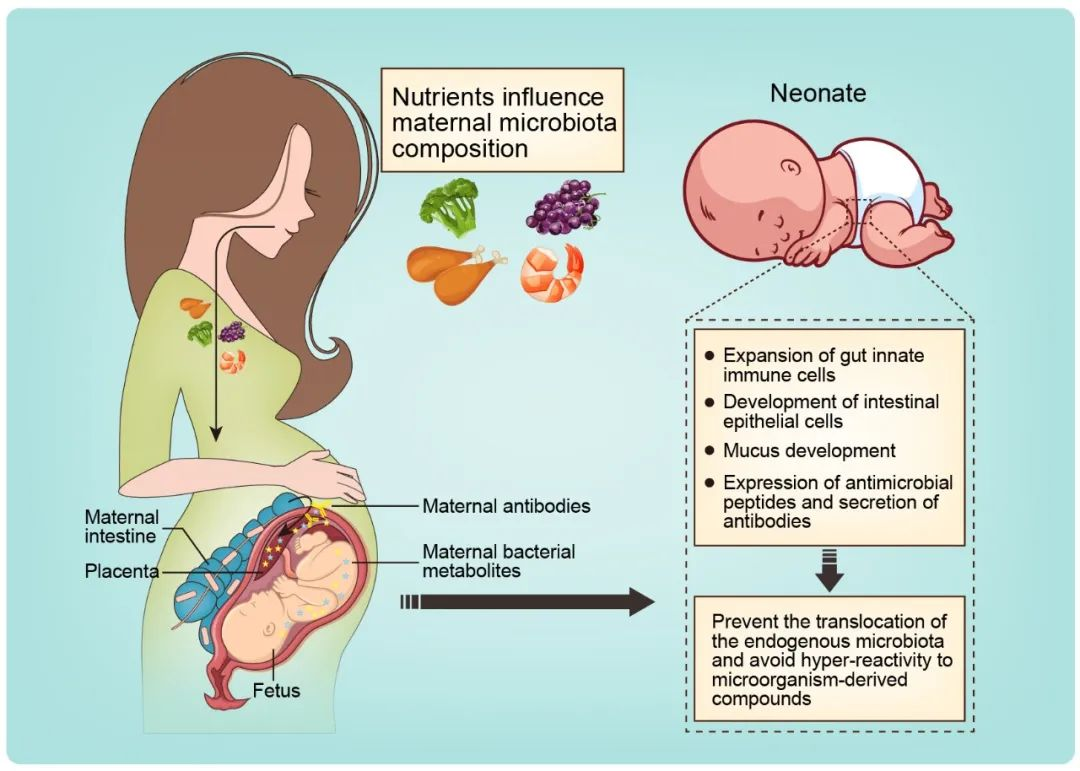

论文插图设计

滑动查看更多 点击查看大图